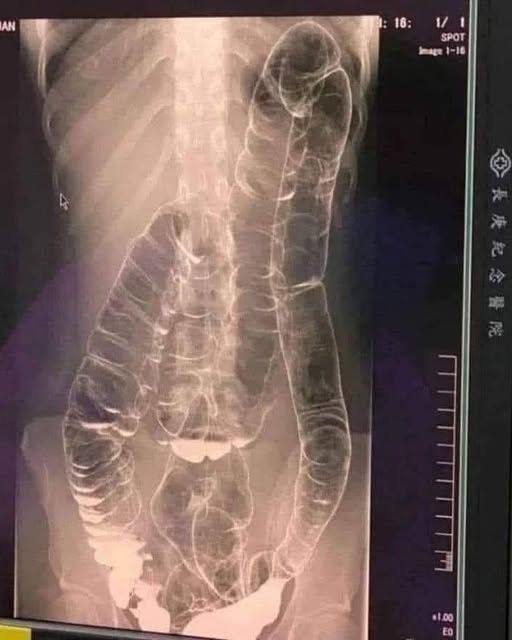

Chronic constipation is a common yet often overlooked condition. In extreme cases, prolonged constipation can lead to toxic megacolon, a life-threatening complication where the colon expands beyond its natural capacity, reaching the chest area and compressing vital organs like the heart.What Happens When the Colon Expands Excessively?

When the colon is unable to expel waste properly, fecal matter accumulates, causing extreme bloating and distension. Over time, the colon loses its natural folds and ability to contract, resulting in:

Severe bowel obstruction

Bacterial overgrowth and toxin buildup

Risk of colon rupture and sepsis